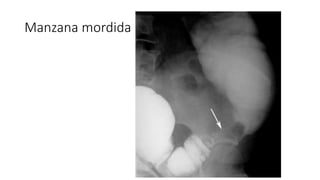

• Linfoma

• Colon por enema: refleja el origen del tumor y si la afeccion en primaria o

secundaria. Si esta extendido sobre un largo segmento aquiere un aspecto de

manzana mordida

• TC: demuestra la extensión del proceso tumoral

• Linfoma • Colonpor enema: refleja el origen del tumor y si la afeccion en primaria o secundaria. Si esta extendido sobre un largo segmento aquiere un aspecto de manzana mordida • TC: demuestra la extensión del proceso tumoral